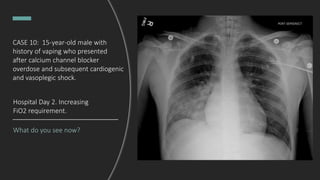

CASE 10: 15-year-old male with

history of vaping who presented

after calcium channel blocker

overdose and subsequent

cardiogenic and vasoplegic shock,

intubated and admitted to

pediatric ICU.

What do you see now?

Hospital Day 2. Increasing

FiO2 requirement.

Right lower lobe consolidation.

Dx: Aspiration pneumonia

Hospital Day 2.

Increasing FiO2 Requirement.